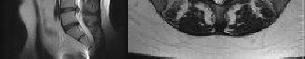

Figures 1 and 2 show sagittal and axial MRI from an 83-year-old woman with an ataxic gait, loss of dexterity, and intermittent loss of bowel and bladder control. The symptoms have been getting progressively worse over the past several weeks.

What disease process is most likely the cause of the patient’s symptoms?

4. Pigmented villonodular synovitis Discussion: B

The patient has a pannus at the C1-2 articulation that is compressing the spinal cord and causing myelopathy symptoms. The development of a pannus at this location has been associated with rheumatoid arthritis. Steinberger and associates showed increased morbidity and mortality when using an anterior approach and the surgery took longer than 4 hours. Chieng and associates showed better outcomes and lower complications rates using a posterior approach.

Question 12 of 100

CLINICAL SITUATION

When discussing anterior versus posterior surgical techniques, you counsel this patient that

Discussion: A